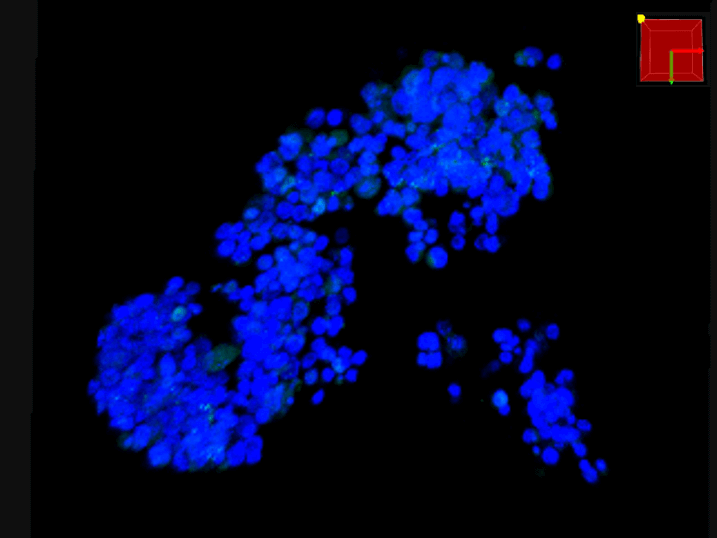

F-PDO®の3D解析

3D解析を用いた形態解析

青…DAPI(核を染色)

赤…actin(細胞骨格を染色)

緑…ZO-1(タイトジャンクションを染色)

3D解析を用いた形態的定量解析

- 青…DAPI(核を染色)

緑…Ki67(増殖細胞のマーカ) - 形態情報(細胞数、容積、Ki67陽性細胞数)を算出

- 細胞塊あたりの細胞数、細胞密度、増殖細胞の比率が算出することができる。

- F-PDO®の種類により、細胞塊の大きさ、細胞密度、増殖細胞の比率はさまざまである。